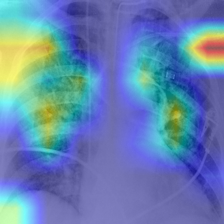

Once the SARS-COV2 reaches the host at the lung, it gets into the cells through a protein called ACE2, which serves as the ”opening” of the cell lock. After the genetic material of the virus has multiplied, the infected cell produces proteins that complement the viral structure to produce new viruses. Then, the virus destroys the infected cell, leave it and infect new cells. The destroyed cells produce radiological lesions [5, 6, 7] such as consolidations and nodules in the lungs, that are observable in the form of ground-glass opacity regions in the XR images (Fig. 1c). These lesions are more noticeable in patients assessed or more days after the onset of the disease, and especially in those older than [8]. Findings also suggest that patients recovered from COVID-19 have developed pulmonary fibrosis [9], in which the connective tissue of the lung gets inflamed. This leads to a pathological proliferation of the connective tissue between the alveoli and the surrounding blood vessels. Given the aforementioned, radiological imaging techniques –using plain chest X-Ray (XR) and/or thorax Computer Tomography (CT)– have become crucial diagnosis and evaluation tools to identify and assess the severity of the infection.

III-E Identification of the areas of significant interest for the classification

The areas of significant interest used by the CNN for discrimination purposes are identified using a qualitative analysis based on a Gradient-weighted Class Activation Mapping (Grad-CAM) [38]. This is an explainability method that serves to provide insights about the manners on how deep neural networks learn, pointing to the most significant areas of interest for decision-making purposes. The method uses the gradients of any target class to flow until the final convolutional layer, and to produce a coarse localization map which highlights the most important regions in the image identifying the class. The result of this method is a heat map like those presented in Fig. 1, in which the colour encodes the importance of each pixel in differentiating among classes.

The regions of interest identified by the network, were analyzed qualitatively using Grad-CAM activation maps [38]. Results shown by the activation maps, permit the identification of the most significant areas in the image, highlighting the zones of interest that the network is using to discriminate. In this regard, Fig. 1, presents examples of the Grad-CAM of a control, a pneumonia, and a COVID-19 patient, for each of the three experiments considered in the paper. It is important to note that the activation maps are providing overall information about the behaviour of the network, pointing to the most significant areas of interest, but the whole image is supposed to be contributing to the classification process to a certain extent.

The second row in Fig. 1 shows several prototipical results applying the Grad-CAM techniques to experiment 1. The examples show the areas of significant interest for a control, pneumonia and COVID-19 patient. The results suggest that the detection of pneumonia or COVID-19 is often carried out based on information that is outside the expected area of interest, i.e. the lung area. In the examples provided, the network focuses on the corners of the XR image or in areas around the diaphragm. In part, this is likely due to the metadata which is frequently stamped on the corners of the XR images. The Grad-CAM plots corresponding to the experiment 2 (third row of Fig 1), indicates that the model still points towards areas which are different to the lungs, but to a lesser extent. Finally, the Grad-CAM of experiment 3 (fourth row of Fig 1) presents the areas of interest where the segmentation procedure is carried out. In this case, the network is forced to look at the lungs, and therefore this scenario is supposed to be more realistic and more prone to generalizing as artifacts that might bias the results are somehow discarded.

This study evaluates a deep learning model for the detection of COVID-19 from RX images. The paper provides additional evidence to the state of the art, supporting the potentiality of deep learning techniques to accurately categorize XR images corresponding to control, pneumonia, and COVID-19 patients (Fig. 1). These three classes were chosen under the assumption that they can support clinicians on making better decisions, establishing potential differential strategies to handle patients depending on their cause of infection [17]. However, the main goal of the paper was not to demonstrate the suitability of the deep learning for categorizing XR images, but to make a thoughtful evaluation of the results and of different preprocessing approaches, searching for better explainability and/or interpretability of the results, while providing evidence of potential effects that might bias results.

We stand on the fact that automatic diagnosis is much more than a classification exercise, meaning that many factors have to be had in mind to bring these techniques to the clinical practice. To this respect, there is a classic assumption in the literature that the associated heat maps –calculated with techniques such as Grad-CAM– provide a clinical interpretation of the results, which is unclear in practice. In light of the results shown in the heat maps depicted in Fig. 1, we show that experiment 1 must be carefully interpreted. Despite the high-performance metrics obtained in experiment 1, the significant areas identified by the network are pointing towards certain areas with no clear interest for the diagnosis, such as corners of the images, the sternum, clavicles, etc. From a clinical point of view, this is clearly biasing the results. It means that other approaches are necessary to force the network to focus on the lungs area. To this respect, we have developed and compared the results with two preprocessing approaches based on cropping the images and segmenting the lungs area (experiment 2 and experiment 3). Again, given the heat maps corresponding to experiment 2, we also see similar explainability problems to those enumerated for experiment 1. Reducing the area of interest to that proposed in experiment 2 significantly decreases the performance of the system due to the removal of the metadata that usually appear in the top left and/or right corner, and to the removal of areas which are of interest to categorize the images but have no interest from the diagnosis point of view. However, while comparing experiment 2 and 3, performance results improve in the third approach, which focuses on the same region of interest but with a mask that forces the network to see only the lungs. Thus, results obtained in experiments 2 and 3 suggest that eliminating the needless features extracted from the background or non-related regions improves the results. Besides, the third approach (experiment 3), provides more explainable and interpretative results, with the network focusing its attention only in the area of interest for the disease. The gain in explainability of the last method is still at the cost of a lower accuracy with respect to experiment 1, but the improvement in explainability and interpretability are considered critical to translate these techniques to the clinical setting. Despite the decrease in performance, the proposed method in experiment 3 has provided promising results, with an Acc of , BAcc of , GMR of and AUC of .

The COVID-Net has also demonstrated being a good starting point for the characterization of the disease. Indeed, the outcomes of the paper suggest the possibility to automatically identifying the lung lesions associated with a COVID-19 infection (see Fig.1) by analyzing the Grad-CAM mappings of experiment 3, providing an explainable justification about the way the network works. However, the interpretation of the heat maps obtained for the control class must be carried out carefully. Whereas the areas of significant interest for pneumonia and COVID-19 classes are supposed to point to potential lesions (i.e. with higher density and/or with different textures in contrast to controls), the areas of significant interest for the classification in the control group are supposed to correspond to a sort of complement, potentially highlighting less dense areas. Thus, not meaning the presence of any kind of lesion in the lungs.